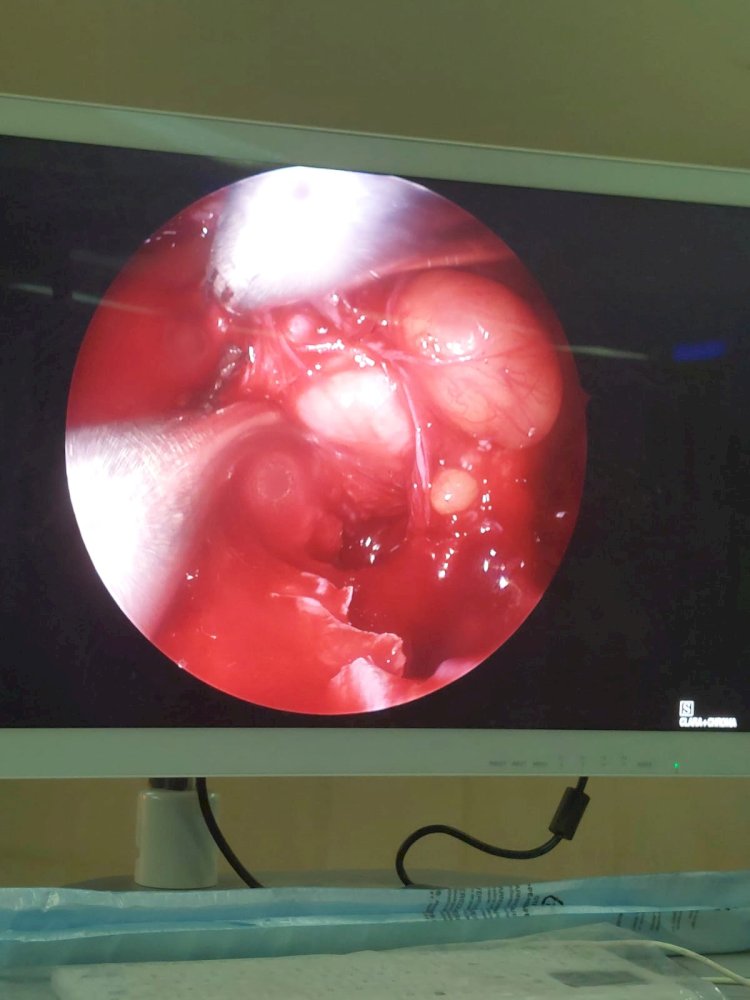

نجح فريق طبي بمستشفي سوهاج الجامعي من استئصال ورم دموي (انجيوفيبروما) بالأنف ممتد إلى الجيب الأنفي الوتدي و ملتصق بالشريان السباتي وممتد إلى المخ، لشاب في مقتبل العمر ١٦ سنة يدعي "ج. ع. ف" بمركز المنشاه، وذلك في عملية استغرقت ٥ ساعات متواصلة.

ومن جانبه أضاف الدكتور محمد عبدالقادر سلطان رئيس قسم الأنف والأذن والحنجرة، أنه علي الفور تم تشكيل فريق طبي علي درحة عالية من المهارة نظراً لخطورة العملية ودقتها، فتم حقن الشرايين المغذية للورم الدموي قبل العملية لتقليل النزيف اثناء العملية بالأشعة التدخلية، وعقب العملية خرج المريض في حالة صحية مستقرة.